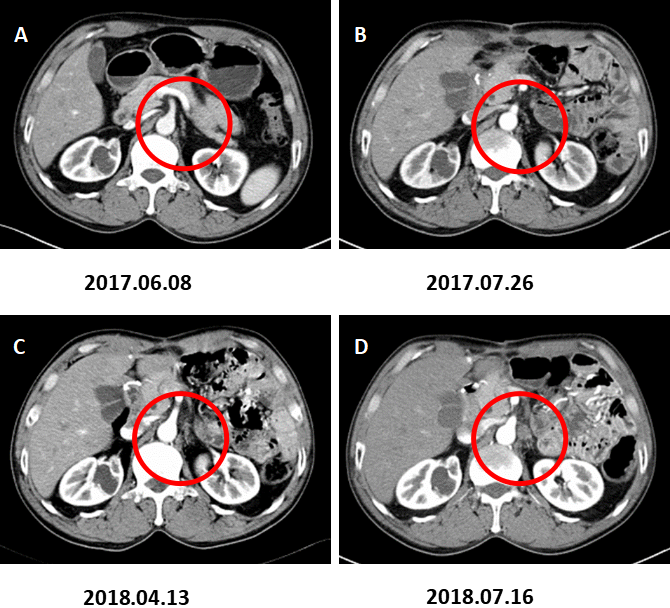

图4. 左肾上腺转移。

A:术前CT增强(2017.06.08)、B:术后CT增强(2017.07.26)、C:术后CT增强(2018.04.13)示左肾上腺增粗,增生考虑。D:术后CT增强复查(2018.07.16)示左肾上腺结节,约2.8×1.8cm,增强后不均匀强化,转移考虑。